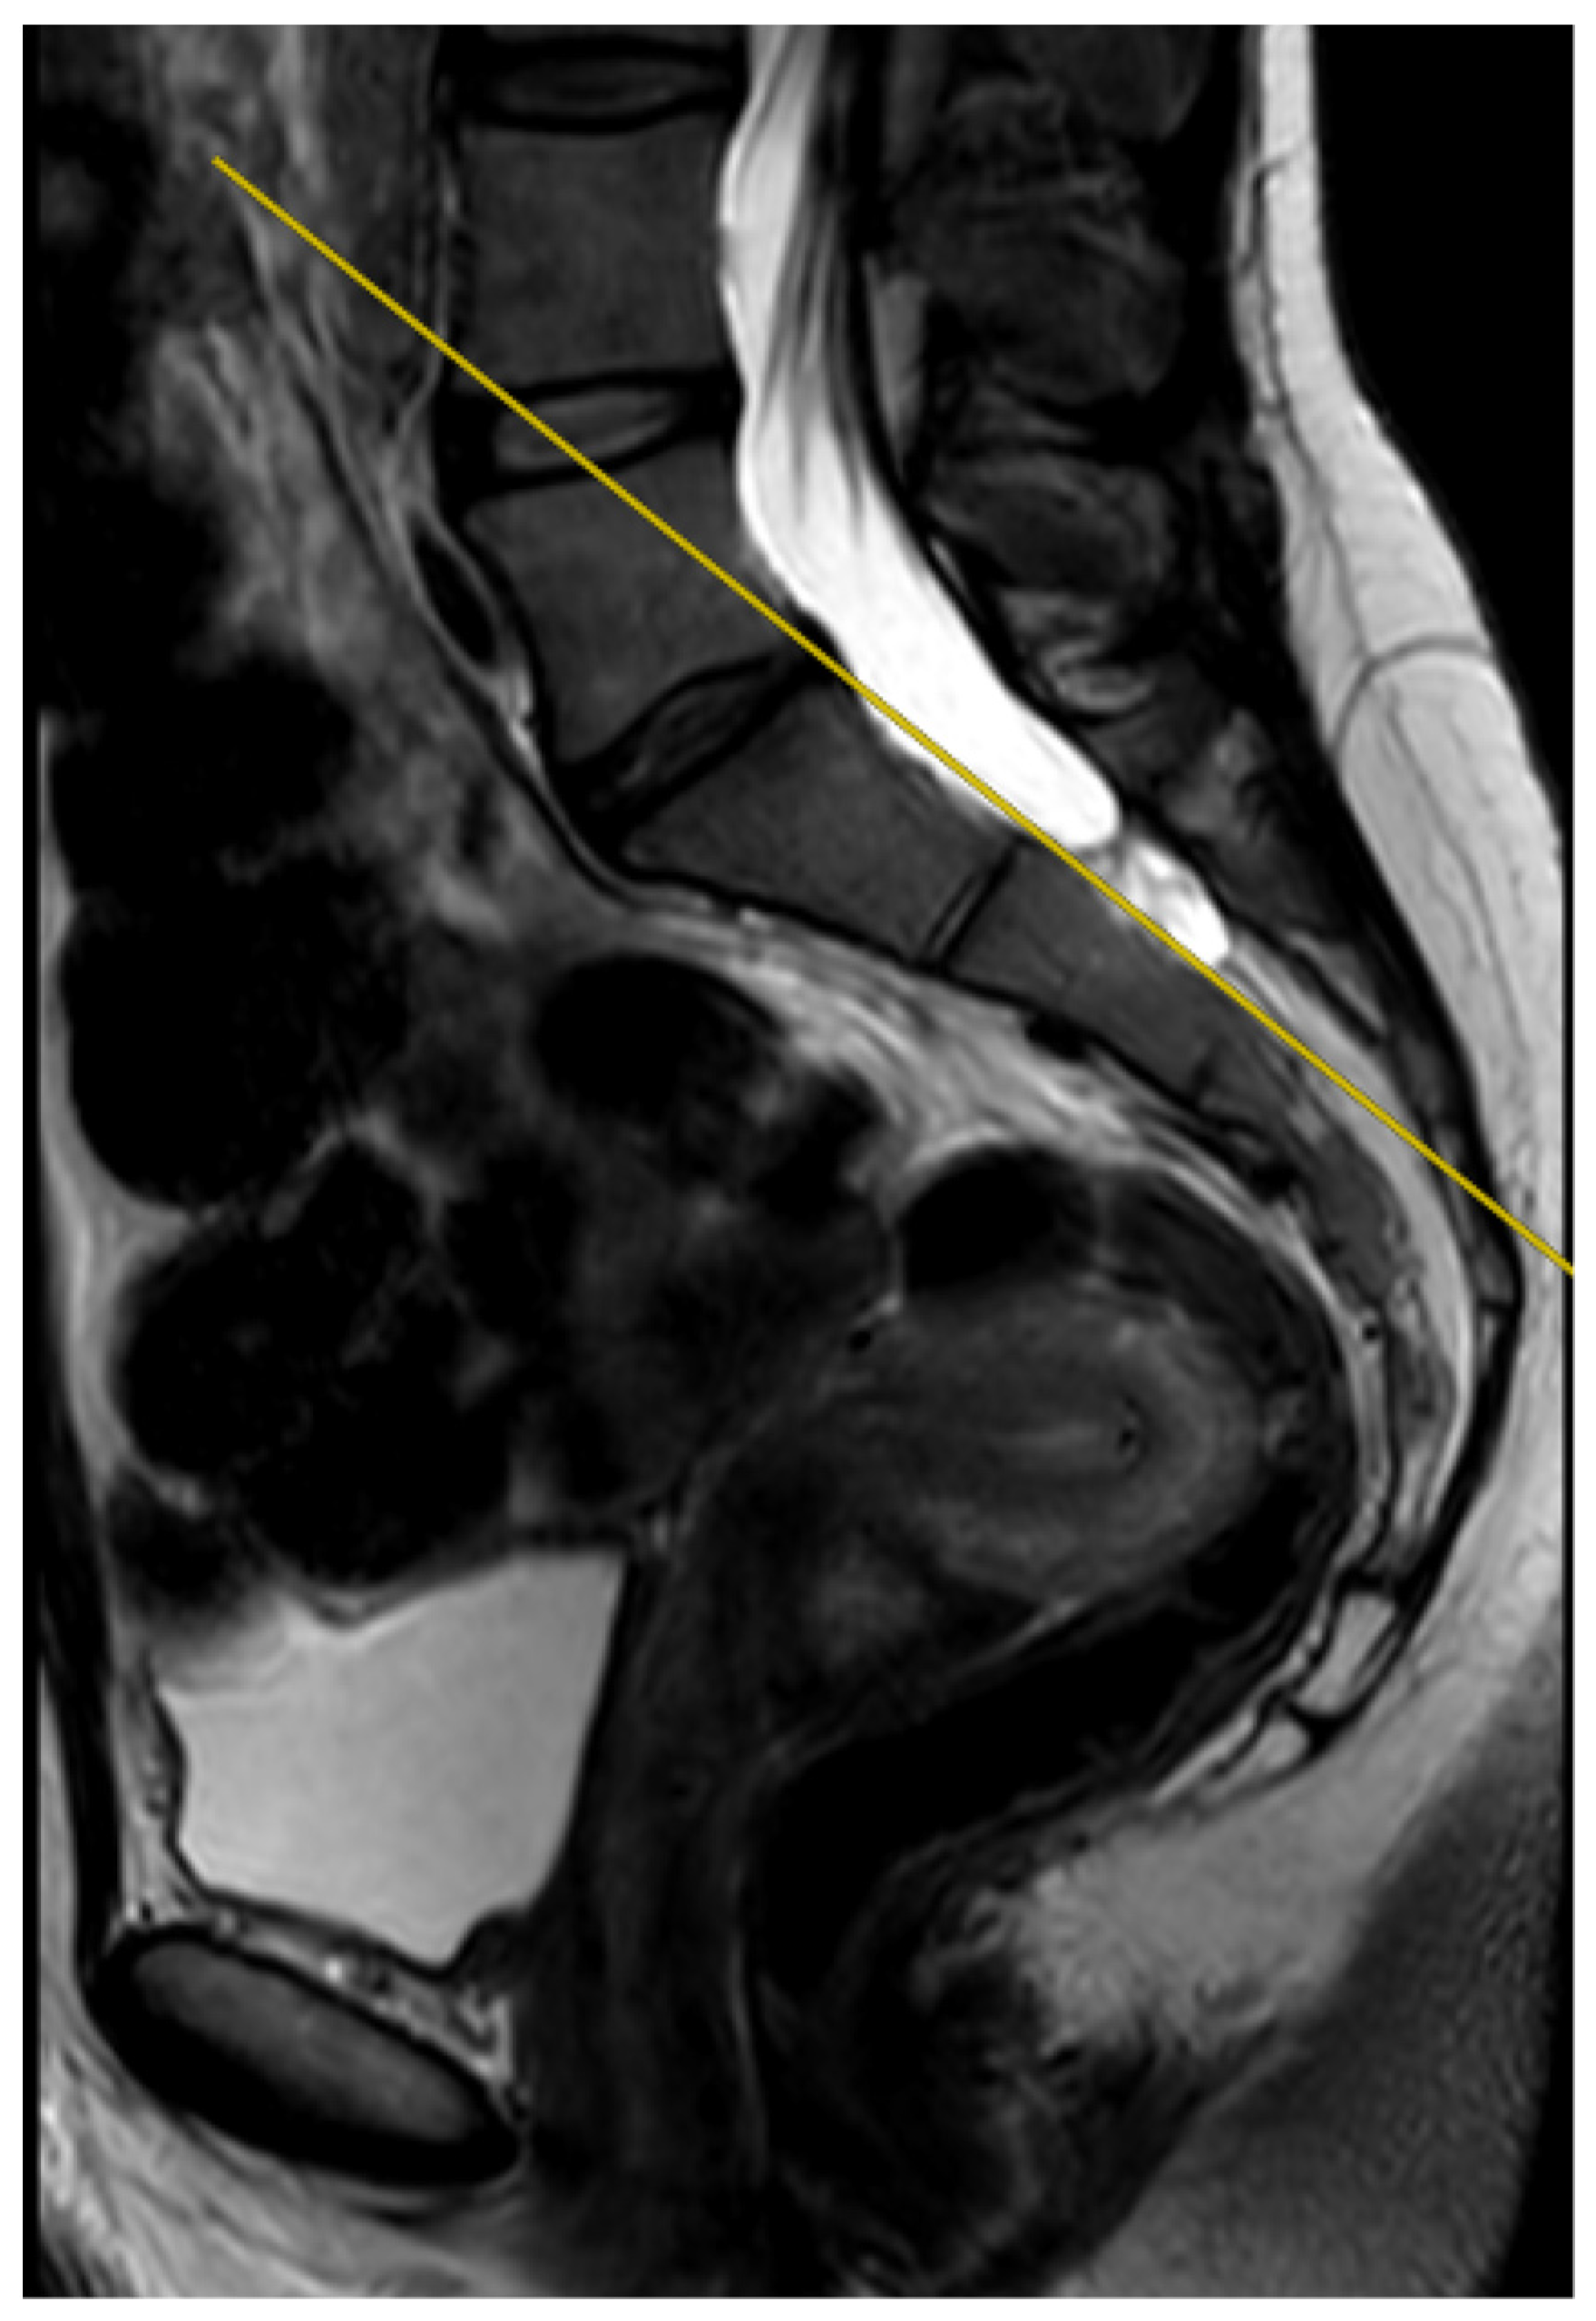

Overall, 20% (n = 35) of the examinations included in the study were performed perfectly correctly considering the technical aspect of the MRI procedure. The examination was defined as fully correct if the deviation angle measured by all of the researchers equaled 0 degrees (Figure 4). The median deviation angle was equal to 5.7 degrees. The maximal deviation angle measured was 29.2 degrees (Figure 5). The ICC (2, 2) was computed as 0.9960 (95% CI [0.9945, 0.9970]), which indicates excellent reliability between the researchers when measuring the deviation angle. Additionally, Figure 6 represents a Bland-Altman diagram with the limits of 95% agreement stated. The results of the division into quartiles due to the deviation angle measurements of all the examinations are shown in Table 1. The obtained division was considered to be valid for the whole study, and on its basis the analysis of the subsequent parts of the study was performed.

Figure 5.

The measured deviation angle equals 29.2 degrees (group 4), T2-weighted sequence. The red line is the fully correct line drawn between the posterior edges of the S1 and S2 vertebrae. The yellow line marks the actual plane in which the slices were acquired.